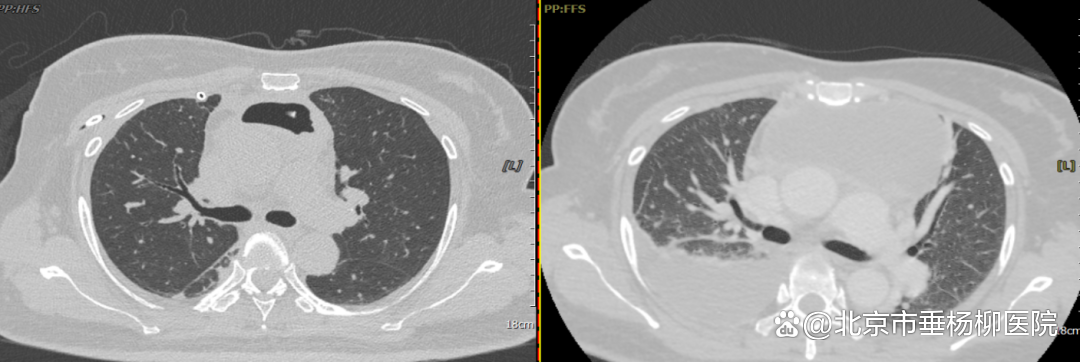

▲术后/术前胸部CT对比